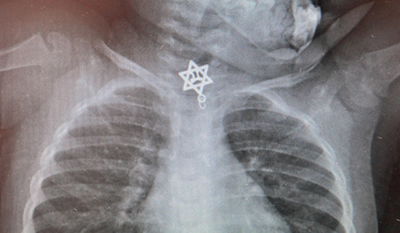

תינוקת בת שנתיים ניצלה לאחר שבלעה תליון בצורת מגן דוד עם הכיתוב "חי". למרבה המזל, התליון נתקע בחלקו העליון של הוושט ונשלף בניתוח חירום על ידי הרופאים (חדשות,בריאות)